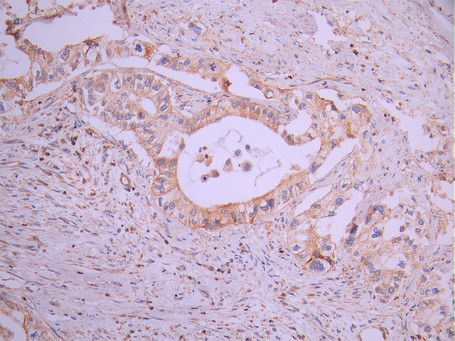

IHC image of CSB-RA272247A0HU diluted at 1:100 and staining in paraffin-embedded human pancreatic cancer performed on a Leica BondTM system. After dewaxing and hydration, antigen retrieval was mediated by high pressure in a citrate buffer (pH 6.0). Section was blocked with 10% normal goat serum 30min at RT. Then primary antibody (1% BSA) was incubated at 4°C overnight. The primary is detected by a Goat anti-rabbit polymer IgG labeled by HRP and visualized using 0.05% DAB.